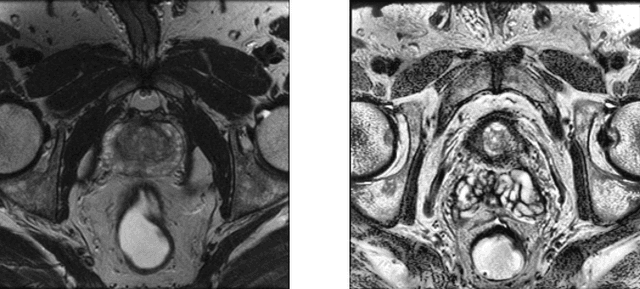

Abstract:Whole gland (WG) segmentation of the prostate plays a crucial role in detection, staging and treatment planning of prostate cancer (PCa). Despite promise shown by deep learning (DL) methods, they rely on the availability of a considerable amount of annotated data. Augmentation techniques such as translation and rotation of images present an alternative to increase data availability. Nevertheless, the amount of information provided by the transformed data is limited due to the correlation between the generated data and the original. Based on the recent success of generative adversarial networks (GAN) in producing synthetic images for other domains as well as in the medical domain, we present a pipeline to generate WG segmentation masks and synthesize T2-weighted MRI of the prostate based on a publicly available multi-center dataset. Following, we use the generated data as a form of data augmentation. Results show an improvement in the quality of the WG segmentation when compared to standard augmentation techniques.